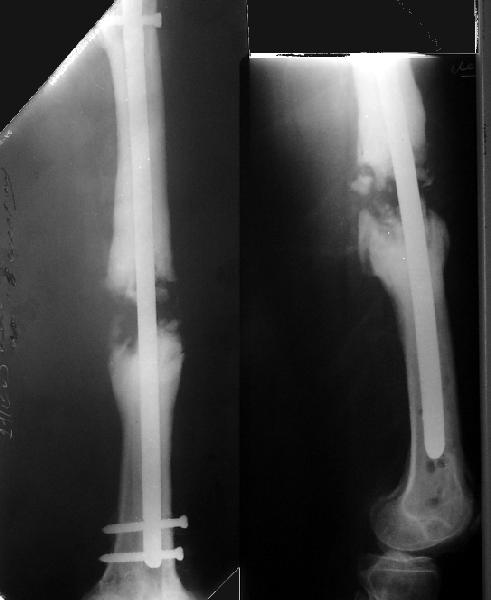

Возможно, проф. Лазарев предложит другой вариант, а в наших условиях мы бы закрыто заштифтовали бы бедро антеградно. Устранили бы варус, используя голень как рычаг, вероятнее всего, даже дистрактор не понадобился бы. В приницпе, можно и ретроградно ири наличии движений в колене, но варус будет труднее устранить - можно и предварительно аппаратом в таком случае.

Стержень можно использовать и обычный потолще, но лучше бы с возможностью введения большего, чем два фронтальных, числа запирающих винтов.

Учитывая наличие этой мощной спайки, запереть можно сразу динамически.

Рефрактур уж точно можно будет не опасаться, а за несколько месяцев даже при отсутствии заполнения костью по всей окружности, этот обходной "мостик" упрочнится и возьмет на себя нагрузку. В приложении пример такого рода "эндопротезирования диафиза", прошло больше 3 лет.